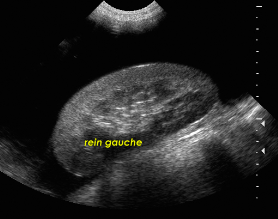

Néphropathie aiguë ou chronique?

aiguë à gauche

chronique à droite

à D : le rein est + petit qu’à G + contours bosselés, irréguliers => chronique. Épaississement du cortex rénal avec hyperéchogénicité du cortex => signe de néphropathie chronique.

à G : cortex est hyperéchogène